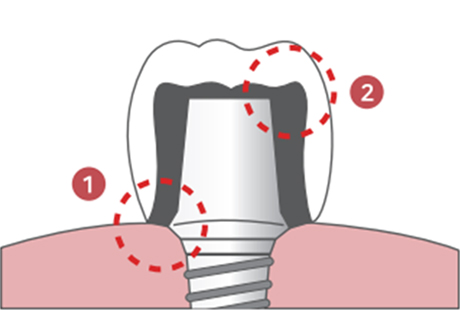

기성 어버트먼트 VS 맞춤 어버트먼트

기성 어버트먼트와 커스텀 어버트먼트 비교

기성 Abutment

기성 Abutment1잇몸과 보철물 사이에 들뜨는 공간으로 음식물 끼임 현상이 생깁니다.

(잇몸염증 유발)2보철물의 안쪽 공간에 비해 얇은 지대주가 저작력을 분산 시키지 못해 보철물이 깨질 위험이 있습니다.